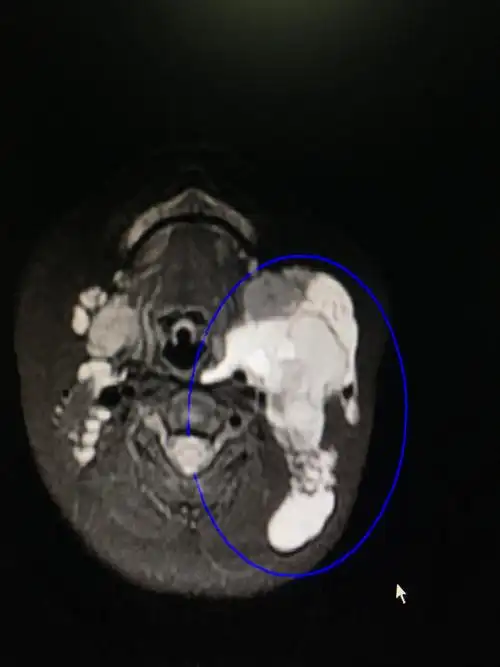

淋巴管瘤,淋巴管畸形如何治疗?能根治吗,会复发吗,留疤吗